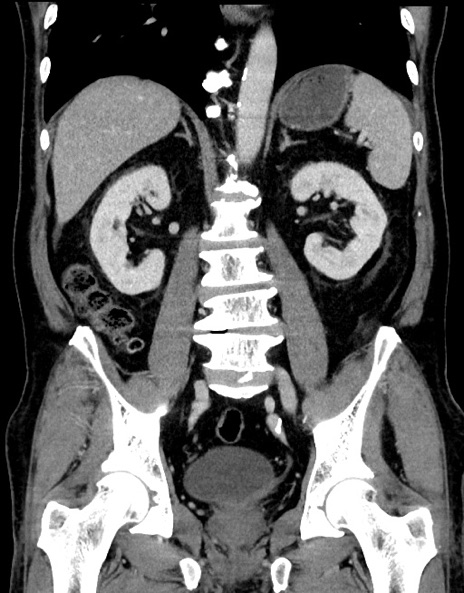

症例15(冠状断像)

【症例】70歳代男性

【主訴】腹痛

【現病歴】今朝から腹痛あり。全体的に痛い。特に左上の方。排ガスが今日はない。冷や汗が出る。

【既往歴】直腸癌術後

【身体所見】左側腹部〜上腹部に圧痛あり。腹膜刺激症状明らかなではない。軽度反跳痛。左下腹部に術後瘢痕あり。